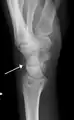

Triquetral fractures can occur due to forceful flexion of the wrist, causing an avulsion of the dorsal aspect of the bone that is often hidden on anterior radiographs, but can be seen as a tiny bone fragment on lateral views.